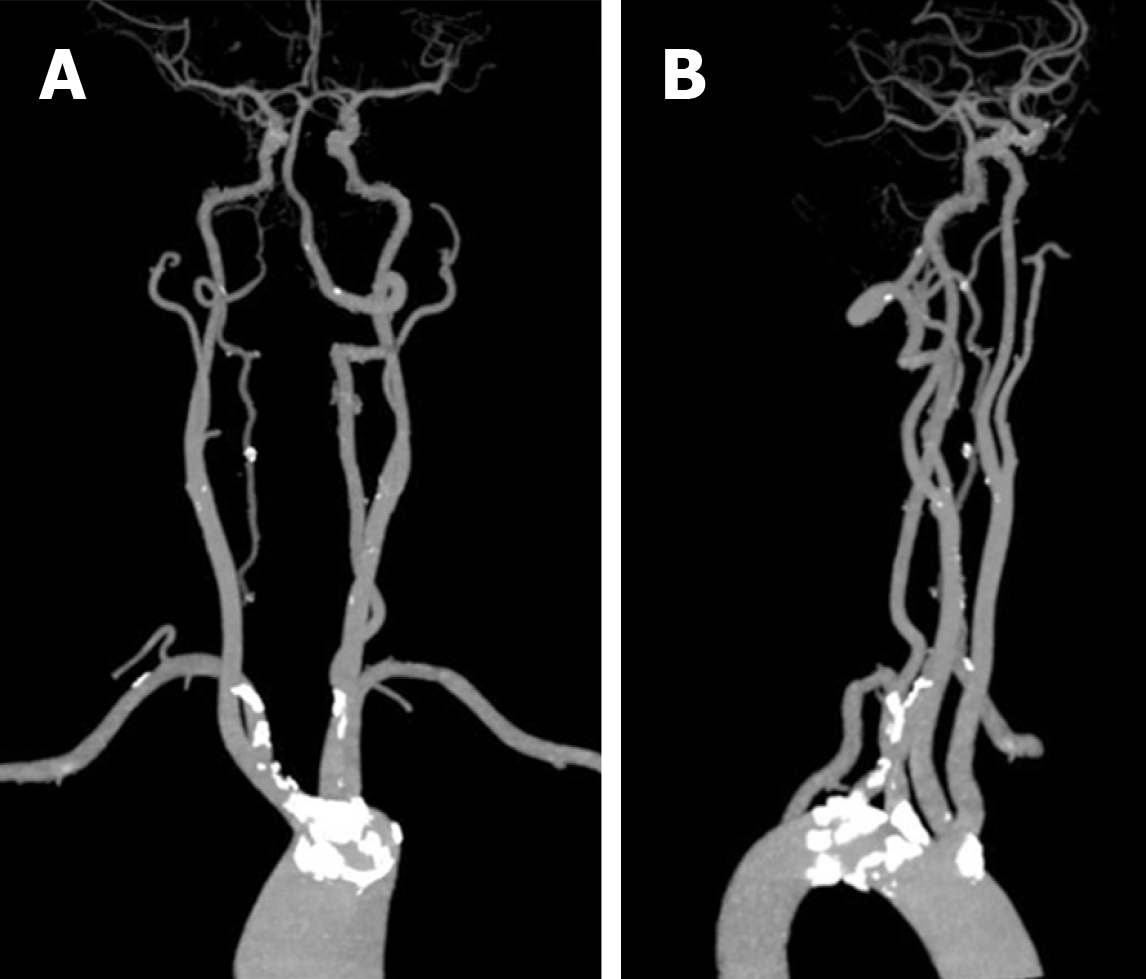

The plaque distribution on middle cerebral artery (MCA) walls. A …

(PDF) Vessel wall differences between middle cerebral artery and …

Bilateral common carotid artery common trunk with aberrant right …

Frontiers | Prospective Study About the Relationship Between CEUS of …

Frontiers | Factors for Enhancement of Intracranial Atherosclerosis in …